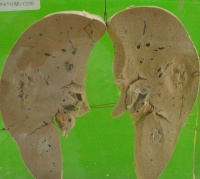

细菌性肝脓肿的致病菌大多为大肠杆菌、金黄色葡萄球菌、厌氧链球菌、类杆菌属等。单个肝脓肿容积有时可以很大;多个肝脓肿的直径则可在数毫米到数厘米之间,数个脓肿也可融合成一个大脓肿。

病程较长的慢性局限性厚壁脓肿,也可行肝叶切除。多发性肝脓肿一般不适于手术治疗。